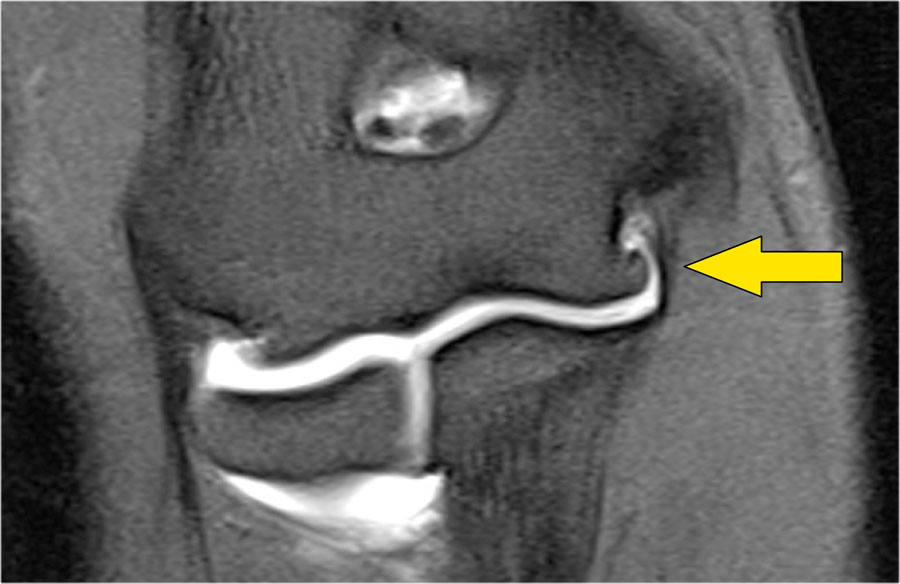

Plica

Cấu trúc này ở phía bên ngoài của khớp đôi khi được nhìn thấy và là một nếp gấp hoạt dịch (plica).

Nó có thể nổi bật và trông gần giống như một sụn chêm.

Đây là một cấu trúc bình thường, nhưng đôi khi nó bị dày lên hoặc không đều và có thể là nguyên nhân gây ra các triệu chứng.